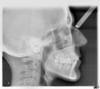

Rédicive d'un traitement dans l'enfance repris avec des gouttières

C-Début 3